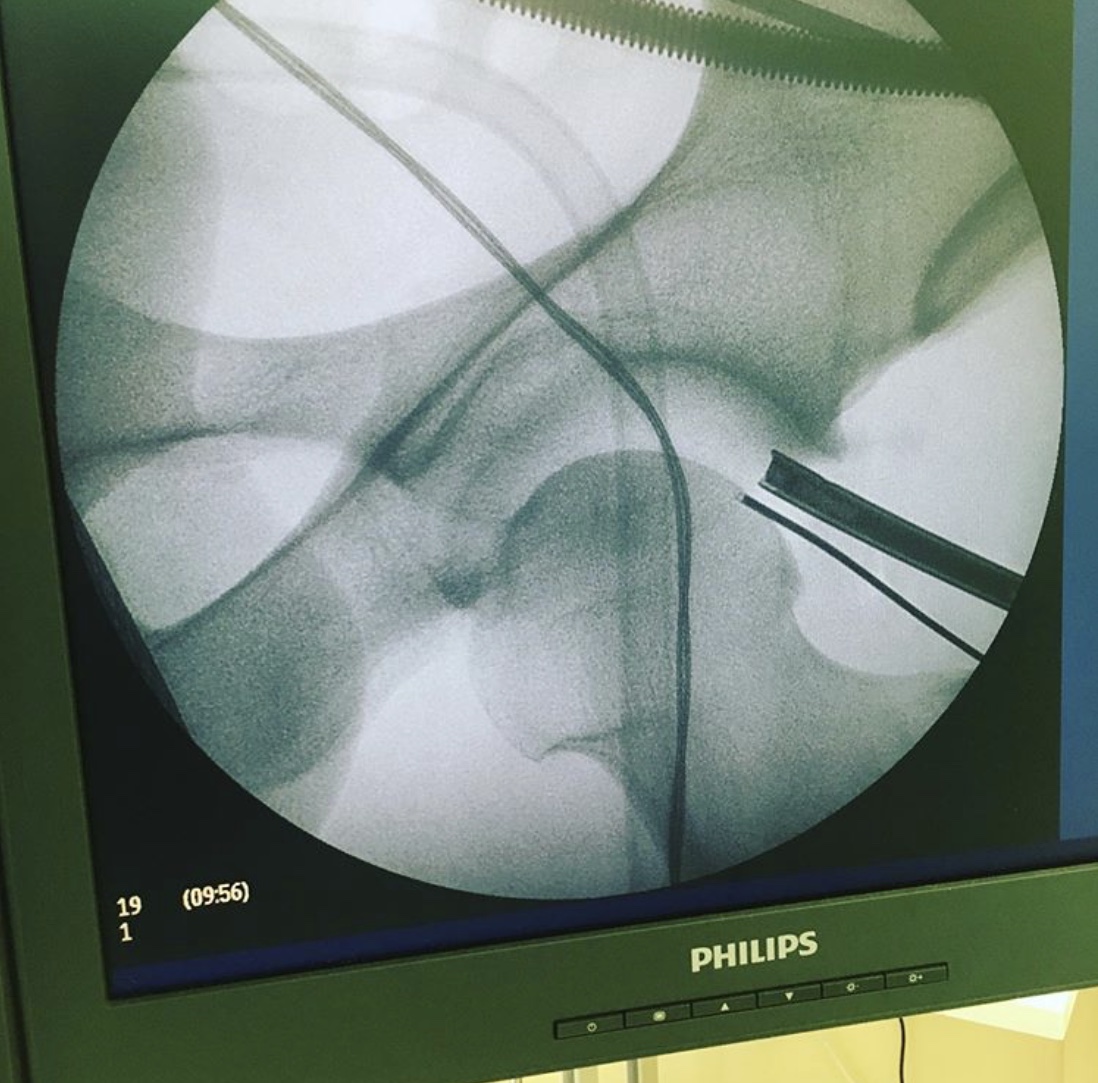

Операция проводится на ортопедическом дистракционном столе (дистракция для расширения суставной щели, желательно не больше 60 минут) . Отмечаются ориентиры.

2 портала для доступа в сустав.

В ходе операции был проведён релиз суставной губы, резекция остеофитов, шов губы левого тазобедренного сустава.